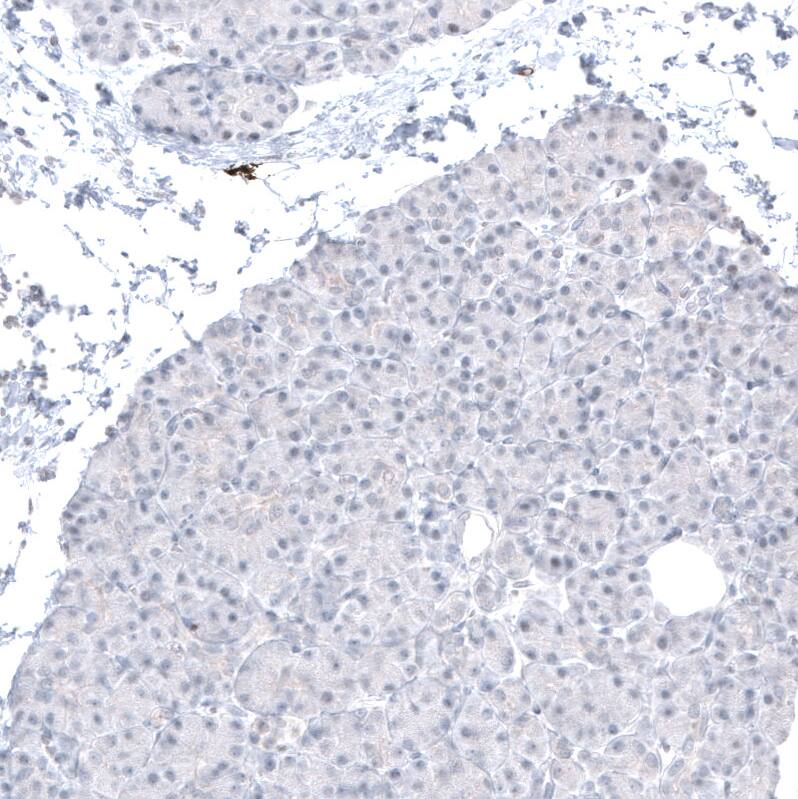

Staining of human pancreas shows no positivity in exocrine glandular cells as expected.